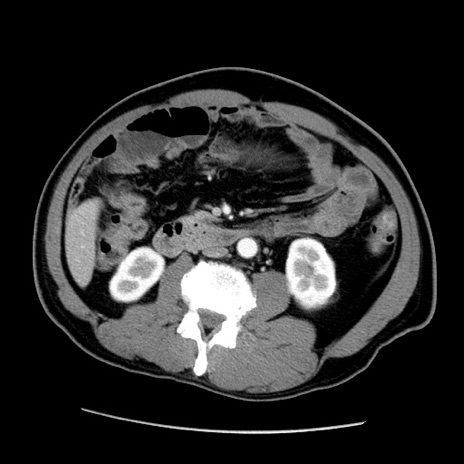

症例22(横断像)

【症例】50歳代男性

【主訴】腹痛

【現病歴】AVMからの被殻出血のため回復期リハ病棟入院中。 本日午後3時頃急に下腹部痛が出現した。

【既往歴】AVM、被殻出血、虫垂炎、高血圧

【身体所見】意識晴明、左半身不全麻痺、会話の理解は良好、36.5°C、腹部:膨隆、全体に板状硬、下腹部正中に圧痛点あり、反跳痛-、筋性防御不明、右下腹部にope scar

【データ】WBC 9400、CRP 0.06